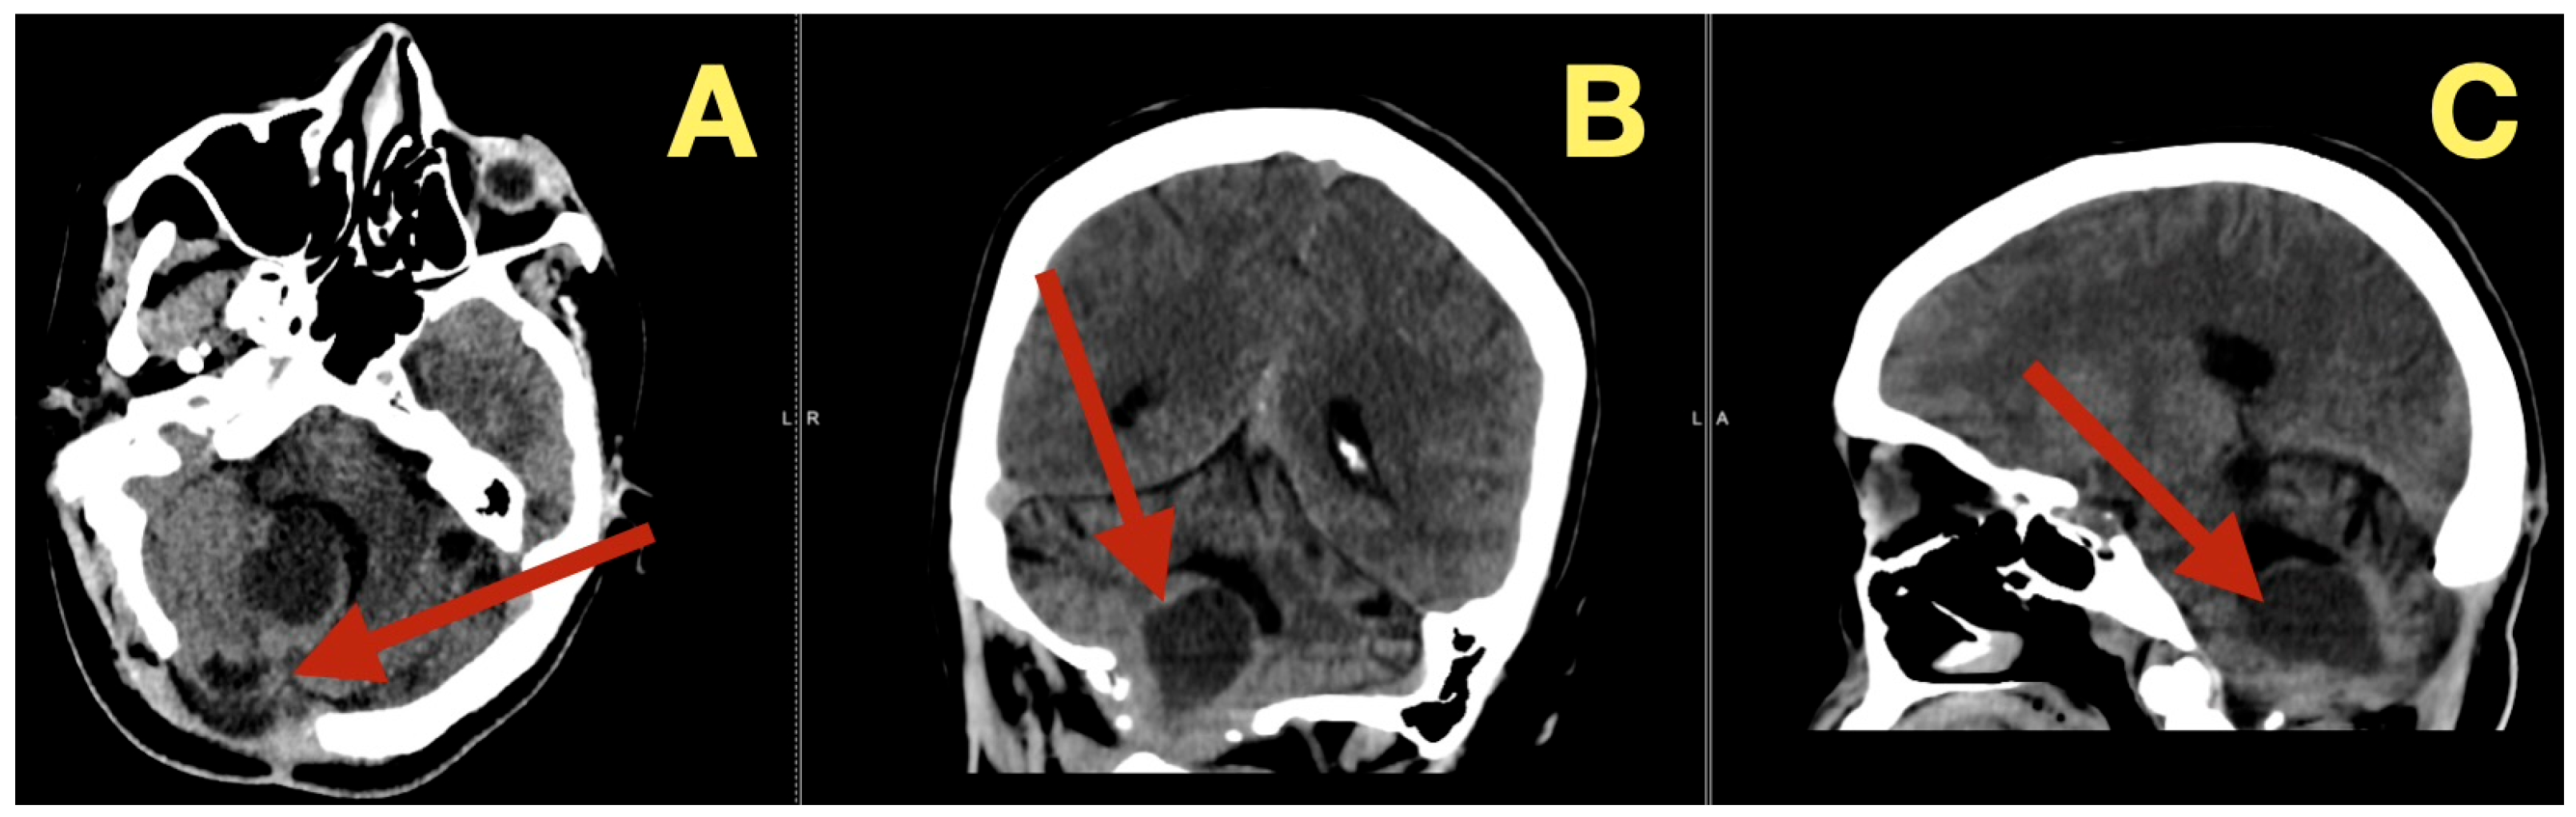

CT scans completed on the first post-operative day (Figure 3) were utilized to exclude hemorrhage and assess early ventricular diameter; they indicated posterior fossa re-expansion, full reopening of the fourth ventricle, normal brainstem convexity, and no early hydrocephalus. A second CT scan completed 7 days post-operatively (Figure 4) verified stable ventricular and outlet patency and excluded late onset hydrocephalus. The one month follow-up CT scan (Figure 5) provided a baseline for long-term comparisons. Later surveillance relied upon MRI including DWI to exclude diffusion-positive residual or recurrence.

Figure 3.

Immediate postoperative CT scan. (A): Axial CT showing full decompression of the fourth ventricle and restoration of normal CSF circulation (arrow). (B): Coronal CT demonstrating complete midline re-expansion with absence of residual mass (arrow). (C): Sagittal CT confirming brainstem relaxation and normalization of posterior-fossa anatomy (arrow).